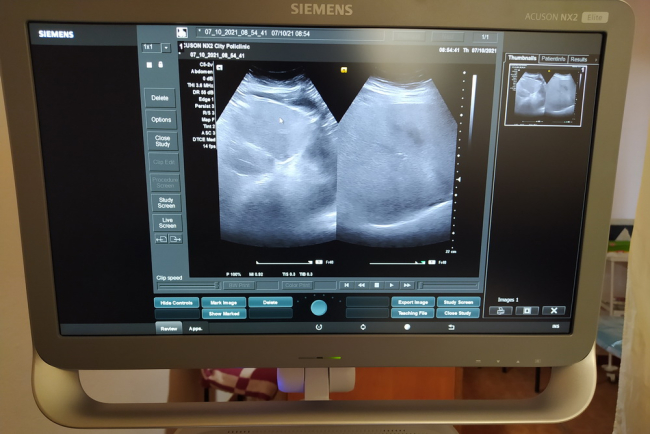

Дубоссары, 7 октября. /Новости Приднестровья/. В поликлинику Дубоссар поступил новый аппарат ультразвукового исследования экспертного класса Siemens. Современное оборудование позволяет проводить необходимые обследования внутренних органов. УЗИ-диагностика является одним из самых информативных неинвазивных методов исследования, позволяющих обнаружить практически любые патологические изменения на ранних стадиях развития.

«Мы получили аппарат высокого класса. На нём можем проводить абдоминальное ультразвуковое исследование, исследование почек, урологические обследования, а также щитовидной и молочной желёз и эхокардиографию. Работать на таком аппарате легко: экран большой и возможности настроек самого изображения хорошие и информативные. У нас в городе и районе всегда УЗИ пользуется спросом, всегда много пациентов», - отметила врач ультразвуковой диагностики Дубоссарской поликлиники Олеся Пануш.